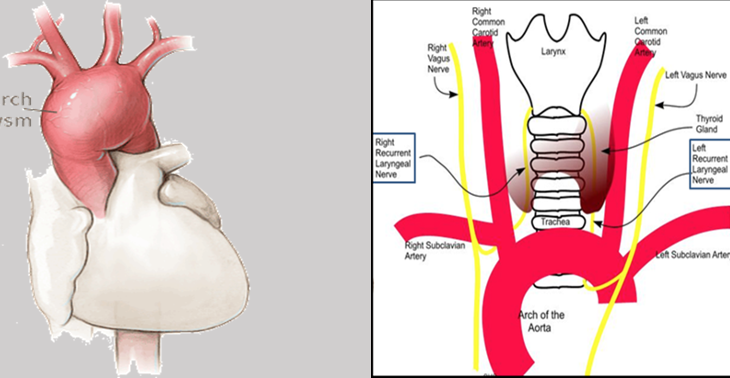

Aortic dissection

What does this refer to

Tear in the inner wall of the aorta (intima) causes blood to flow into the middle layer (media) and force the layers apart

Aortic dissection

Stanford Typing System Aortic Dissection

What does this refer to

Most commonly in the aortic arch or L subclavian

Always include in differential of chest pain

Typically c/o severe sharp, “tearing” (ripping) sensation in the chest or back

Be suspicious of dissection in high risk patients c/o pain radiating to the back

Pain may migrate as the dissection extends

Stanford Type A-chest pain anteriorly—may hear new murmur in aortic area

Stanford Type B-may see pain between scapular areas/back pain.

Neck or jaw pain may occur with involvement of aortic arch

Pertinent Historical findings/clinical Sx Aortic Dissection